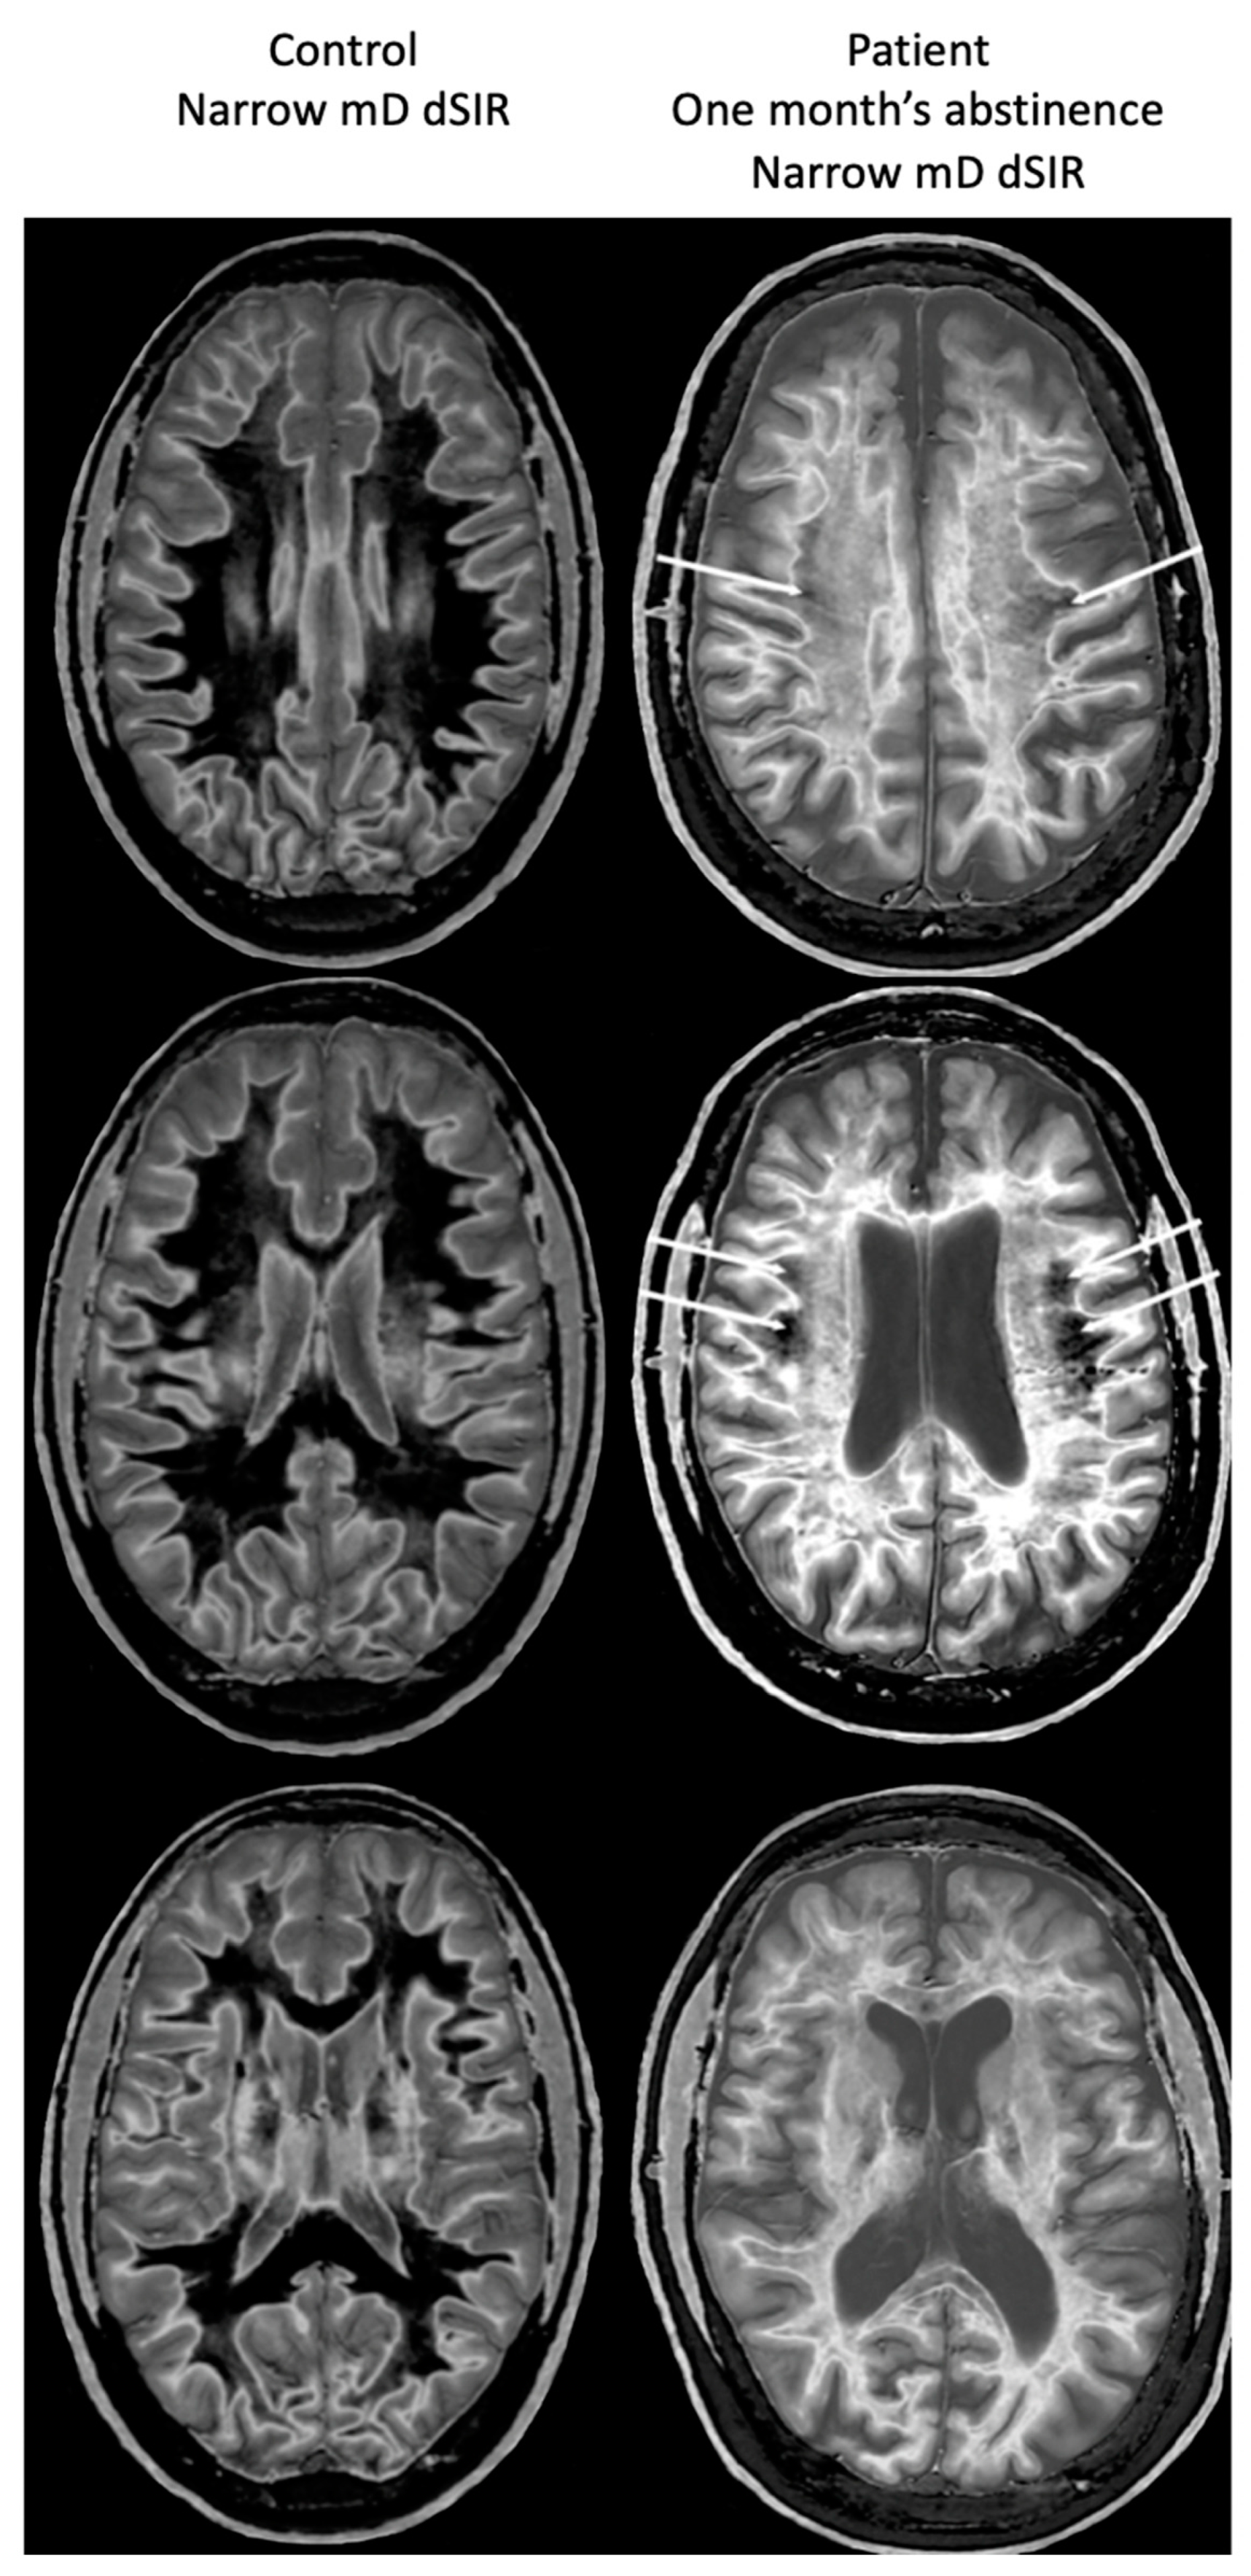

Figure 17, left column shows narrow mD dSIR images from the 50-year-old normal control (left column) and from the patient at his initial MR examination after one month’s abstinence. The normal control shows a very low signal (dark) appearance in most of his white matter. There is an intermediate signal and higher signal in and around the corticospinal tracts (whiteout sign grade 1). In the right column, the patient’s white matter shows extensive areas of high signal with only small areas of more normal lower signal white matter present in the periphery (white arrows) (whiteout sign grade 4).

Figure 17.

A 50-year-old normal control (left column) and Case 1, a 51-year-old with methamphetamine use disorder (right column). 2D dSIR narrow mD images are shown. The narrow mD dSIR images in the normal control show most white matter as very low signal intensity (dark) with a mid gray and lighter appearance in and around the corticospinal tracts, i.e., whiteout sign grade 1. The narrow mD dSIR images in the patient show widespread high signal changes in white matter with only small areas of normal dark white matter at the periphery of the white matter (white arrows). The features are consistent with a whiteout sign grade 4. Normal high signal boundaries are seen between white matter and gray matter on the dSIR images in the control and the patient, but are less obvious in the patient because of the high signal in his abnormal white matter.

There is a dramatic difference between normal white matter on the left which is black and abnormal white matter on the right which is white (apart from small spared or relatively spared areas).